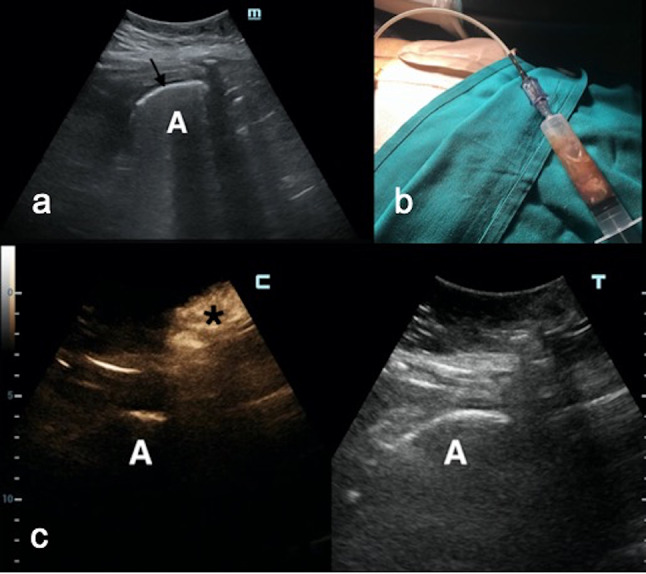

Fig. 1.

a A left subdiaphragmatic abscess (a) was displayed around the spleen (S) in a 40-year-old man after bariatric surgery. b After catheter positioning, the abscess cavity (between white arrows) was barely recognizable, whereas the catheter tip was not seen. B-mode scan was blurred with blood due to procedural trauma (S = Spleen). c IC-CEUS enabled the localization of the catheter inside the collection (white arrows) and the visualization of the real extension of the abscess; no extravasation into the adjacent splenic parenchyma was noted

Demonstration of the correct position of the catheter/needle in 100% of the cases. This check proved especially relevant in cases of small targets, difficult sites (e.g., subdiaphragmatic) or when the US B-mode image was blurred because of the presence of either air or blood, the latter being caused by procedural trauma inside the abscess (Fig. 1).